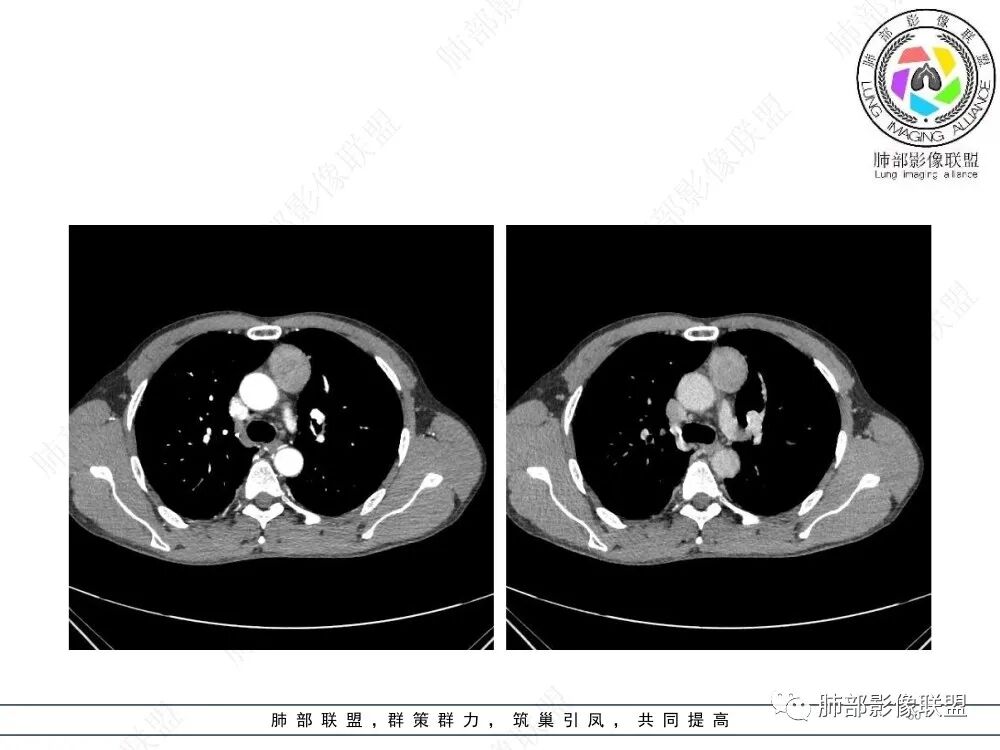

放射小白:男性47岁,前纵隔团块状占位,边界尚清,增强中度强化,内部疑似纤维分隔,常规考虑胸腺瘤可能(A/AB型),鉴别类癌、CD。

瑞欣:中年男性,检验未见明显异常,前纵隔软组织快影,边界清,可见明显强化,首先考虑胸腺瘤,鉴别淋巴瘤,畸胎瘤,生殖细胞瘤。

金豆:晨读:定位前纵隔,膨胀性生长,质地中等,边界清,有浅分叶,中等强化,似乎有裂隙低密度,常规胸腺瘤(B1)。

Yishion:晨读:纵隔占位,偏侧生长,边界清楚,有浅分叶,强化明显,其内似见纤维分隔,常规考虑胸腺瘤(AB型)。

蓝天白云:晨读:47岁男,前纵隔占位,边界清,有浅分叶,中等强化,胸腺瘤(B1)。

宇宙:前纵膈偏左类圆形肿块,边界清晰光整,与大血管脂肪间隙清,密度均匀,轻中度强化,考虑胸腺瘤,A型?鉴别胸腺癌。

玫:男,47岁,咳嗽,咳痰一年,前纵隔软组织密度肿块影,边界清晰,内密度均匀,增强扫描轻度强化,考虑胸腺瘤可能。

周太狼:中年男性,前上纵隔胸腺区软组织团块占位,边界清,增强中度强化,内密度较均匀,常规考虑胸腺瘤。

月亮圆了!:前纵隔包块,边界清,有分叶,密度不均,中等强化,考虑胸腺瘤。

衡妈🇨🇳:中年男性,前纵隔偏左侧实性占位,密度相对均匀,边缘分叶,周围脂肪结构略模糊,增强后动脉期不均匀强化,有低密度区,纤维分隔显示不清。考虑胸腺瘤B1 B2型。

朱伟超:中年男性,前纵膈偏离中线肿块,浅分叶,内有分隔,中等不均匀强化,常规胸腺瘤。

流心明智:男,47,咳嗽、咳痰1年余。胸部CT:前纵膈偏左类圆形肿块,瘤肺界面清晰光整,纵隔侧部分层面絮状影?平扫密度较均匀,增强后轻度强化,内可见宽带及线样低密度分隔。邻近左上肺受压凹陷。考虑胸腺肿瘤,AB型?胸腺Ca?鉴别淋巴瘤、N源性肿瘤、CD等。

2、影像特点:前纵隔偏左侧软组织影,密度相对均匀,未见明显包膜钙化及实质内钙化,局部边缘浅分叶,周围脂肪间隙密度增高、浑浊,未见侵犯大血管、未见纵隔内淋巴结转移、未见侵犯心包内结构、未见胸膜转移结节、未见肿块沿着纵隔胸膜蔓延,未见胸腔积液。增强后动脉期不均匀强化,未见明显纤维分隔。